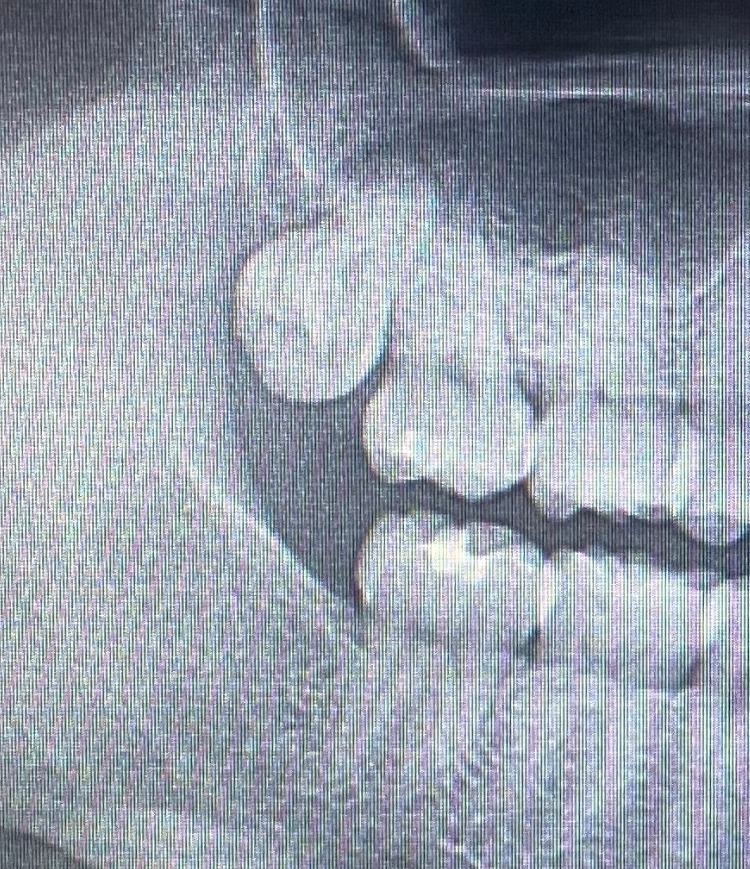

칠이 벗겨진 치과 의자에 눕는다. 이윽고 다가온 덴티스트 황. 입을 벌린 지 1초 만에 으음 심플 아니야 한 달 있다 와! 뭐여 왜 반말이여. 하지만 그 당당한 반말에 나는 욕쟁이 할망구 맛집에 온 듯한 신뢰를 느낀다. 선생님 사랑니가 썩었나요? 썩긴 뭐가 썩어! 이제 야금야금 나고 있구먼. 아니 36살이구만, 사랑니가 날 군번이 아니거든? 거 참 희한하네. 한 달 뒤에 와. 아니 선생님 제가 너무 아파서 왔거든요. 당연히 아프지!! 생살 찢고 뚫고 이가 나는 건데. 안 아프면 더 이상해!!

잇몸 뚫고 그렇게 나고 잇는 나의 사랑니